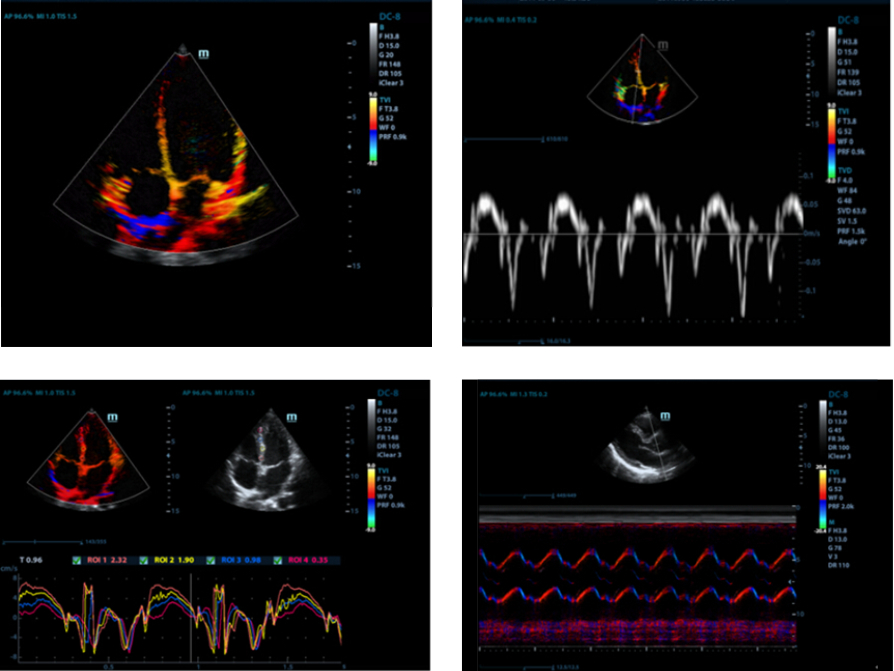

Free Xros CM?

Evaluaci├│n precisa del movimiento en diferentes fases y sincronizaci├│n simult├Īnea del miocardio. Provee alta velocidad de cuadros, proporcionando resultados precisos.

TDI

El diagn├│stico por imagen en modo doppler tisular (TDI) permite evaluar cuantitativamente el movimiento mioc├Īrdico local y su funci├│n, proporcionando as├Ł modos TDI para un diagn├│stico m├Īs r├Īpido y directo.

Auto LV

Procedimiento de medici├│n simple del ventr├Łculo izquierdo mejorado gracias a la funci├│n de seguimiento autom├Ītico y f├Īcil correcci├│n manual.

Fracci├│n de eyecci├│n autom├Ītica (AutoEF)

Una forma inteligente de analizar las 2D para reconocer autom├Īticamente los niveles diast├│licos/sist├│licos y generar la estimaci├│n diast├│lica, el volumen diast├│lico, la fracci├│n de eyecci├│n (EDV/ESV/EF), etc. resultantes del m├®todo Simpson.